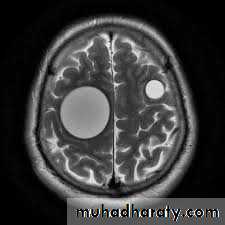

5. Hydatid cyst of brain

Brain occasionally affected, produce mass effect.Other organs, Bones, muscle, Kidney, heart and pancrease.

The most serious type of cysticercosis is neurocysticercosis which can lead to epilepsy , lesion in the brain , blindness and tumor like growths and be can be fatal.

3-MRI or CT scan of the brain.